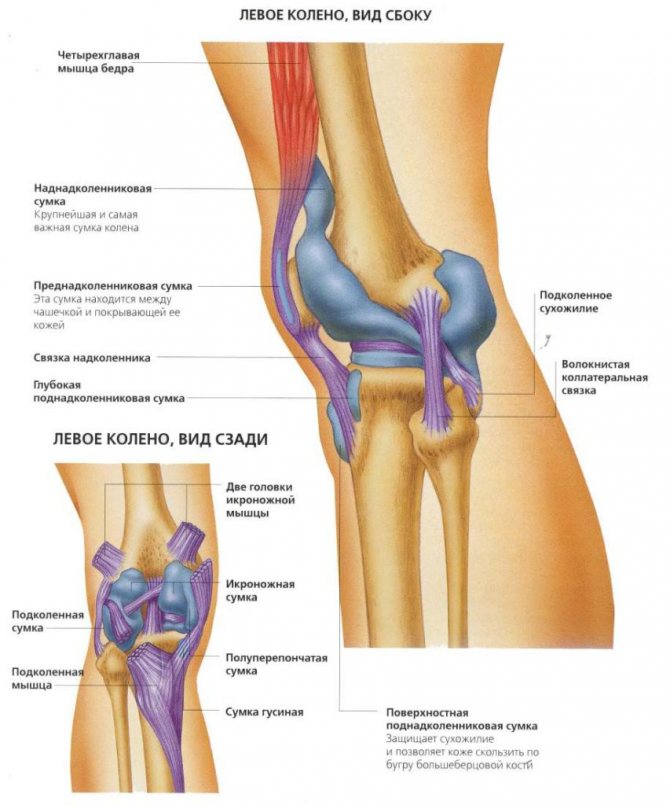

Коленный сустав формируют бедренная, большеберцовая кость и надколенник. Кости соединяет между собой и фиксирует связочный аппарат, который включает в себя такие элементы:

- коллатеральные (боковые) связки — большеберцовая и малоберцовая;

- задние связки — подколенная, дугообразная, медиальная, латеральная и собственная связка надколенника;

- внутрисуставные — крестообразные, а также поперечная связка колена, соединяющая мениски.

Ежедневно наши колени выдерживают огромные осевые и безосевые нагрузки. Справляться с ними они могут лишь благодаря уникальному строению. Коленные суставы имеют свои анатомические особенности. Изнутри они укреплены крестообразными связками, а между суставными поверхностями формирующих их костей находятся мениски. Подобное строение позволяет коленям справляться с возложенными на них функциями.